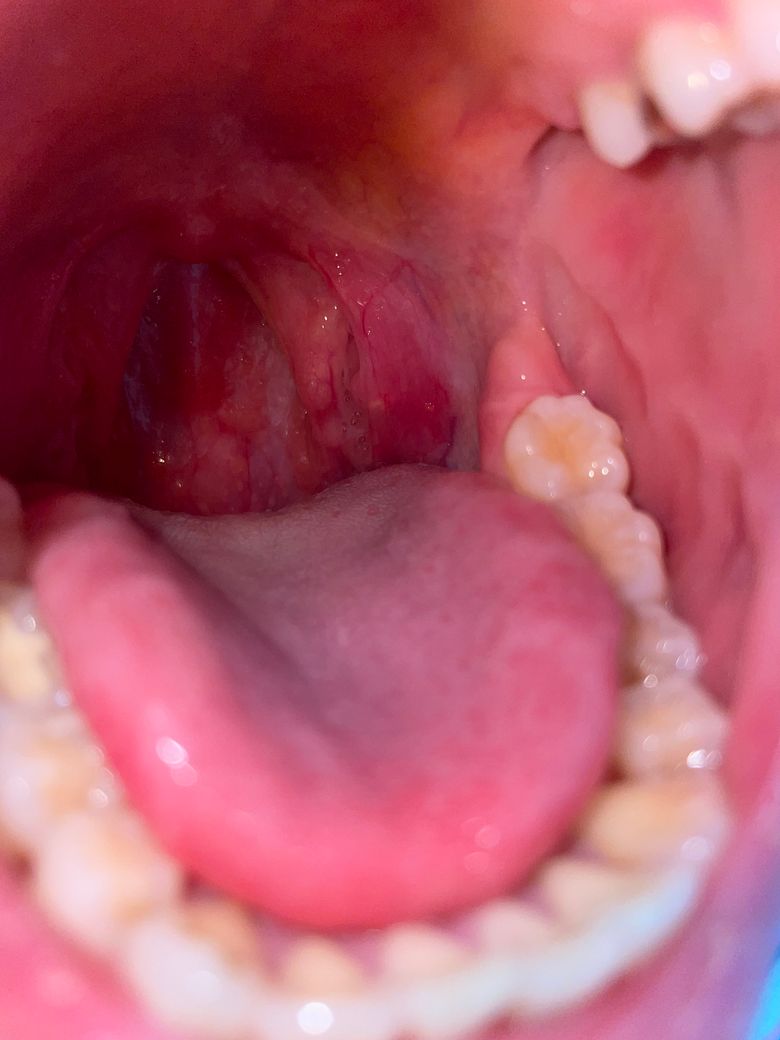

입안 뾰루지랑 편도쪽 부음 무슨증상인가요?

이빈후과에선 신경쓰지말라고 하는데 아무래도 계신경이 쓰이네요 신경안써도 될까요?? 뾰루지랑 편도쪽 비대칭 이상없는지 궁금해요

네 사진상으로 봤을때 이상 소견은 관찰되지 않습니다. 현재 말씀하신 부분이 증상을 따로 일으키지 않기 때문에 지켜보시기 바랍니다.